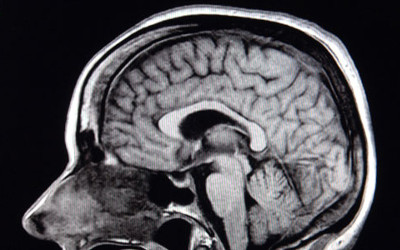

The results of that experiment, described in the March 23 Journal of Neuroscience, add to evidence that the amygdalae, small, almond-shaped brain structures tucked deep in the brain, aren’t the only bits of the brain that make a person feel afraid.

The twins, called B.G. and A.M., have Urbach-Wiethe disease, a genetic disorder that destroyed most of their amygdalae in late childhood. Despite this, the twins showed fear after inhaling air laden with extra carbon dioxide (an experience that can create the sensation of suffocating), an earlier study showed. Because carbon dioxide affects a wide swath of the body and brain, scientists turned to a more specific cause of fear that stems from inside the body: a drug called isoproterenol, which can set the heart racing and make breathing hard. Sensing these bodily changes provoked by the drug can cause anxiety.